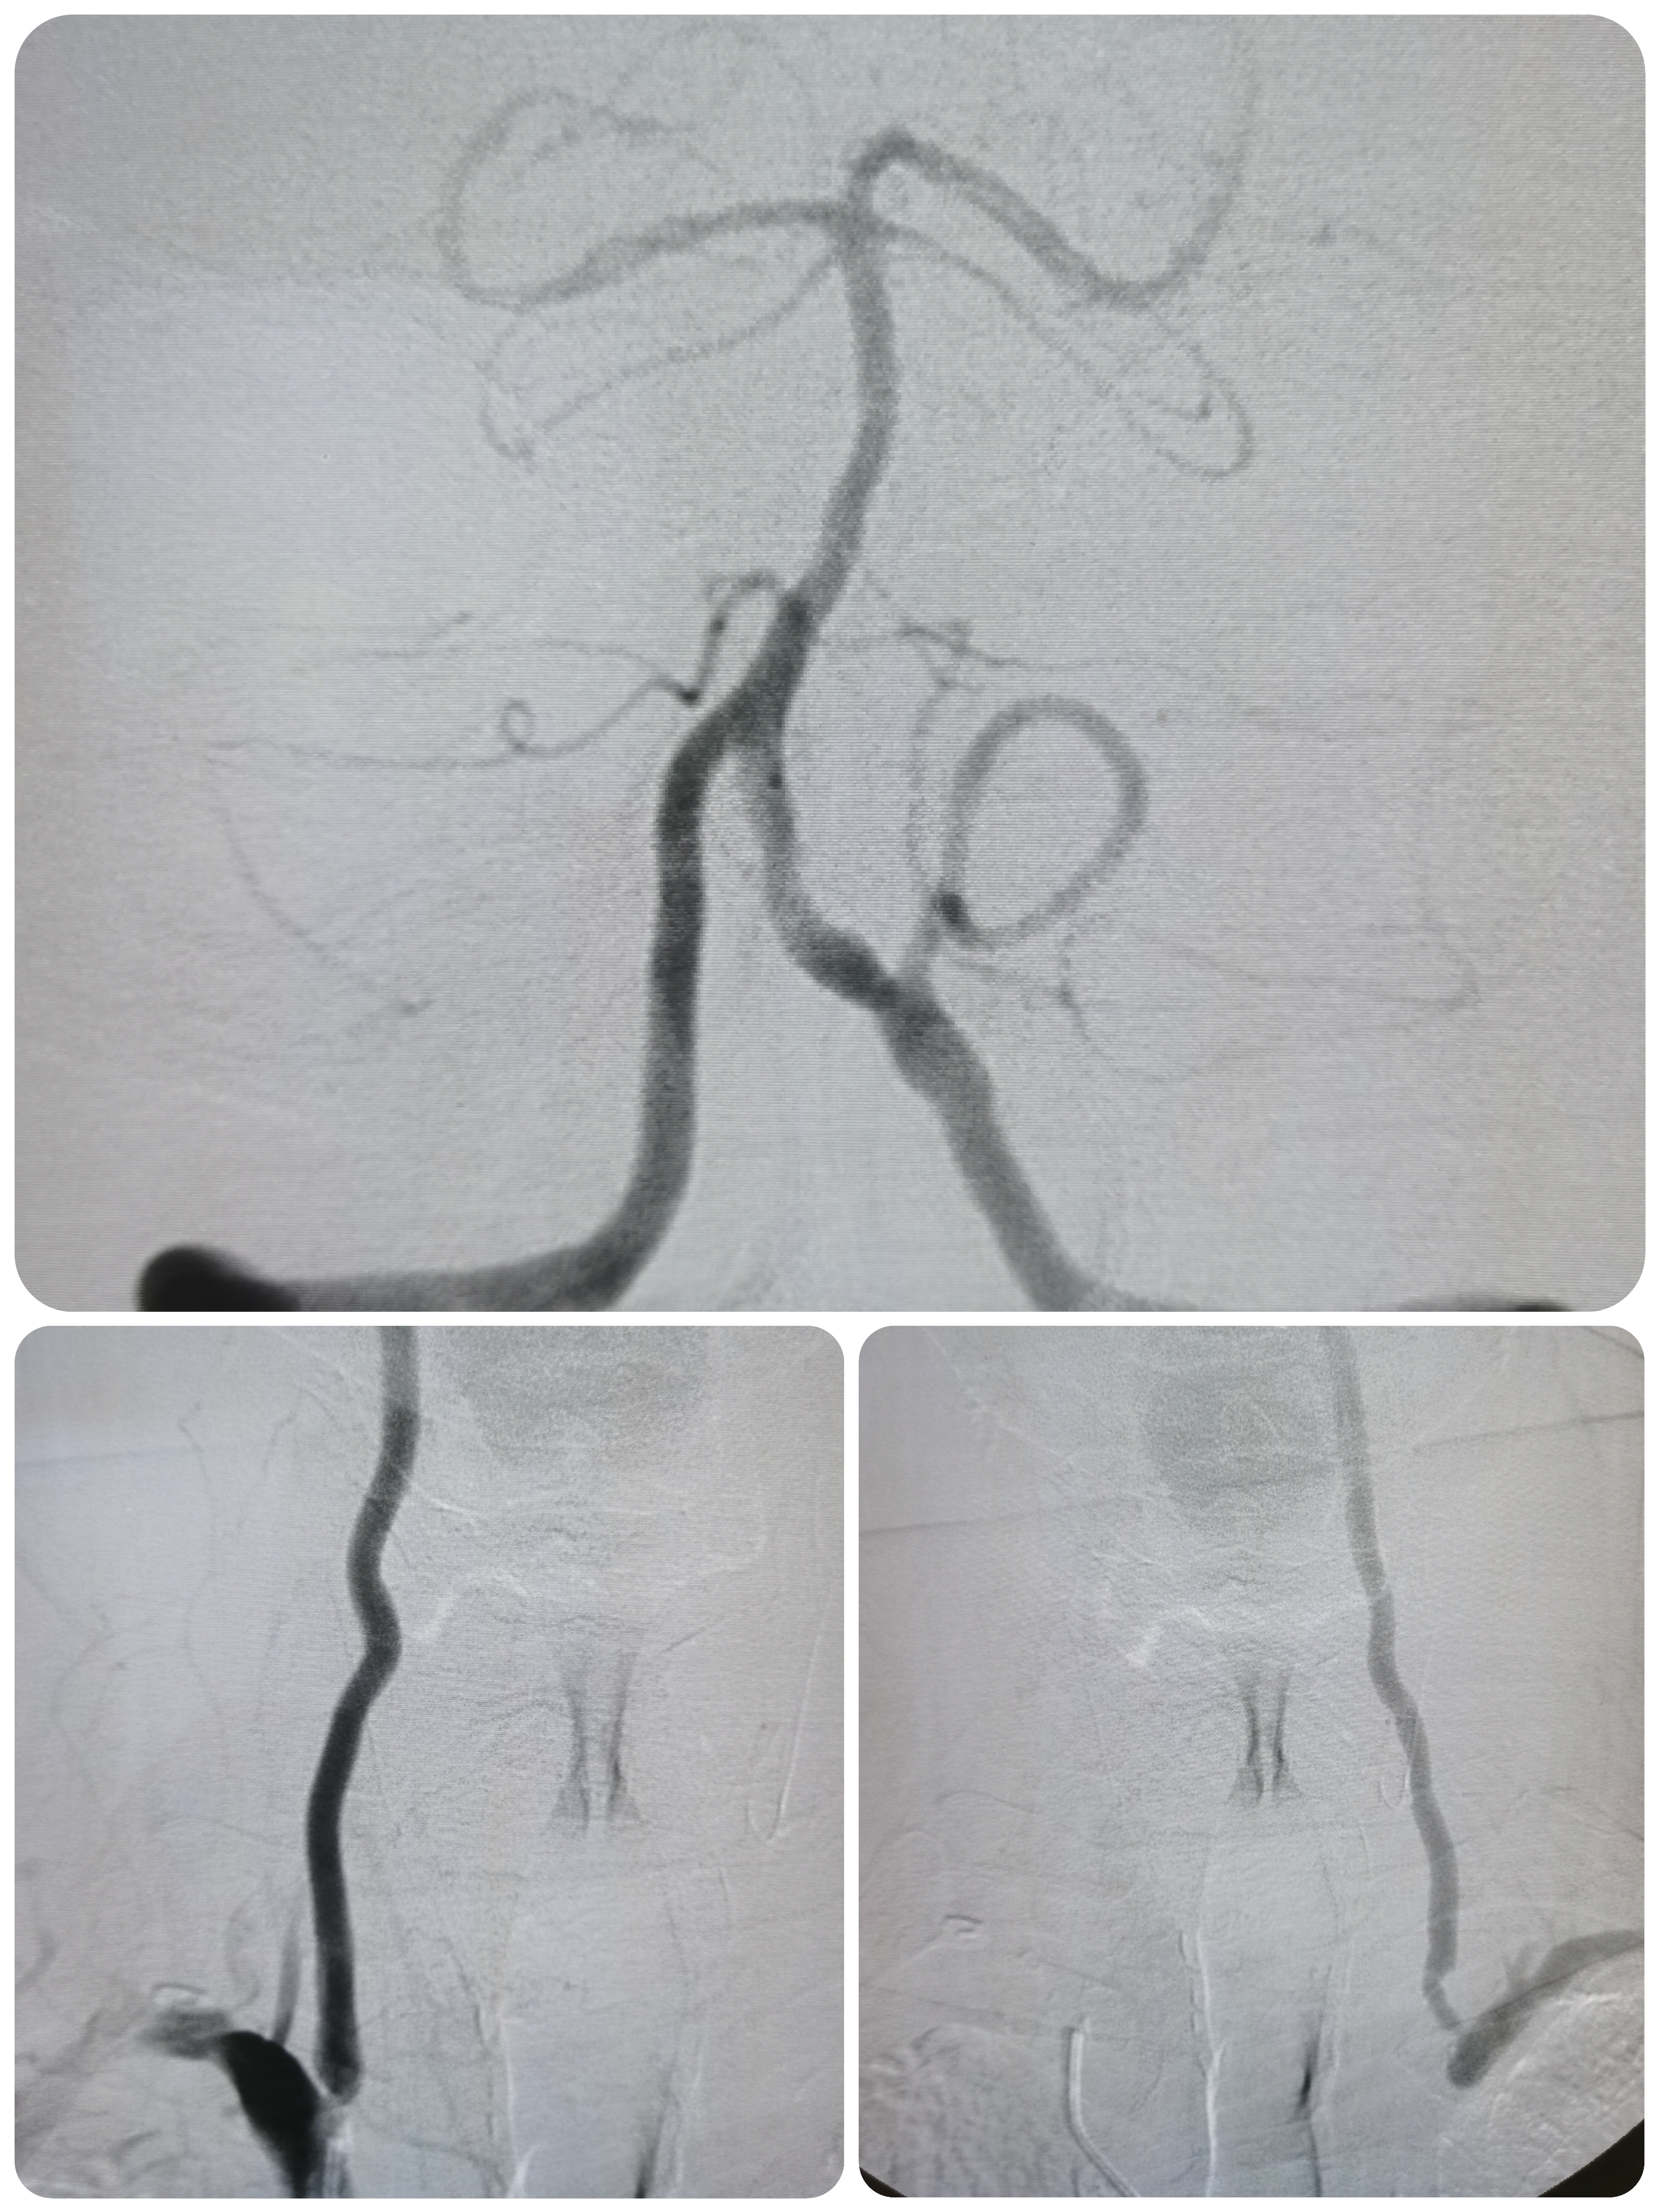

右椎动脉起始部极重度狭窄。

右颈内动脉窦部重度狭窄,局部斑块不稳定。

左侧锁骨下动脉起始部完全闭塞。

1、造影明确左侧锁骨下动脉起始部完全闭塞,右椎造影可见左椎返流,晚期可见圆钝的锁骨下动脉闭塞端,结合病史考虑闭塞时间较长。

2、右椎动脉起始部极重度狭窄,系责任血管。

3、右侧颈内动脉起始部重度狭窄,局部斑块不稳定,且右侧后交通动脉开放。